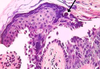

INCONTINENTIA PIGMENTI

(IP), VESICULAR STAGE

Neutrophilic spongiosis

DDX:

- psoriasis

- subcorneal pustulosis

- AGEP

- dermatophytosis

- bacterial infections

- Reiter’s syndrome